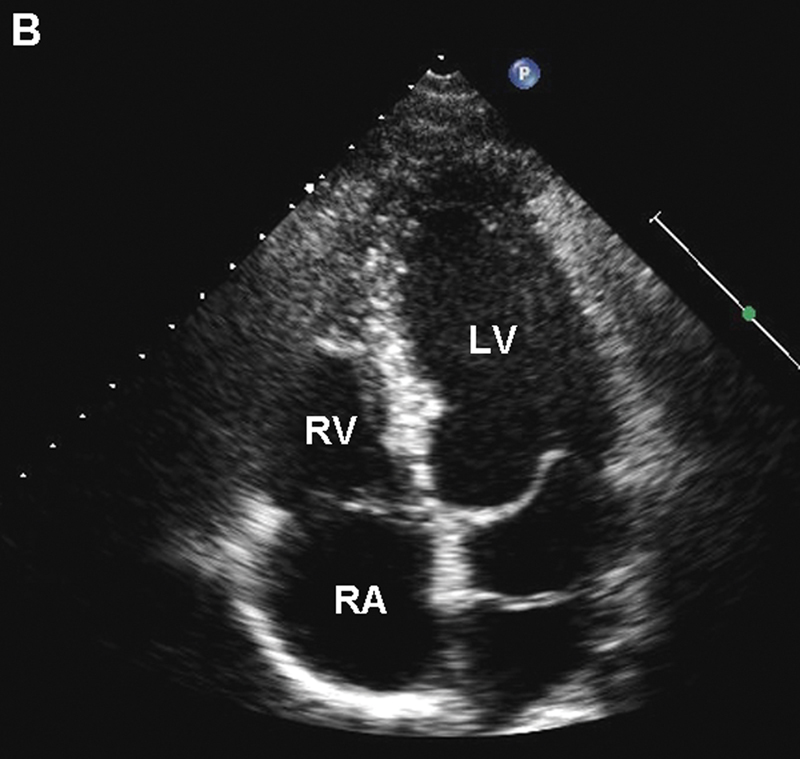

فحوصات تشخيصية لبعض امراض القلب والشرايين التاجية